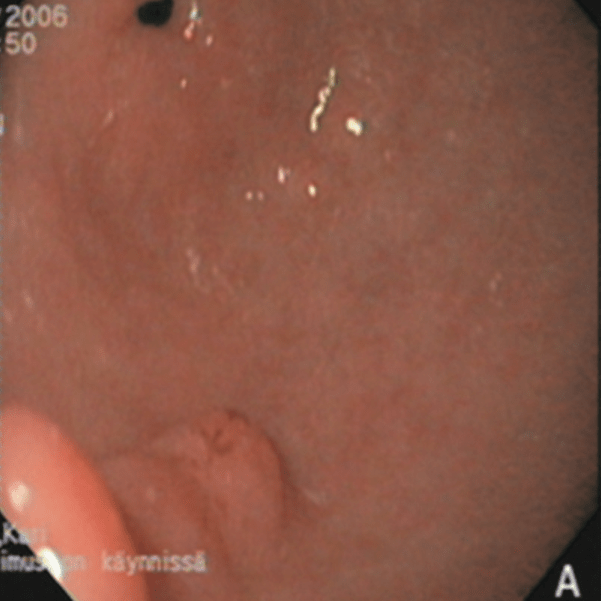

#EndoQuiz: Какой тип по Toljamo?

#EndoQuiz: Правильный ответ - Неполная эрозия (II тип), подтип IIb - участок повреждения эпителиального слоя на возвышении